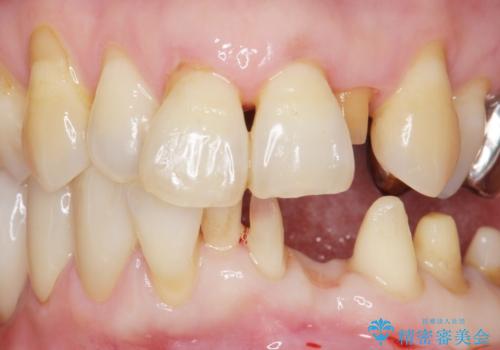

入れ歯も抵抗があるとのことから、相談を重ね、今の状態では保存不可能な下の前歯(左下2)を抜去し、ブリッジや連結補綴により動揺を抑えることにしました。

また、咬み合わせが反対になっている上の前歯(左上2)も補綴で形を変えることにより、咬合を改善しました。

下顎大臼歯が欠損したままで今ある歯に負担がかかりやすいことから、長期的予後は保証できないことをご理解頂いた上で治療を行いました。